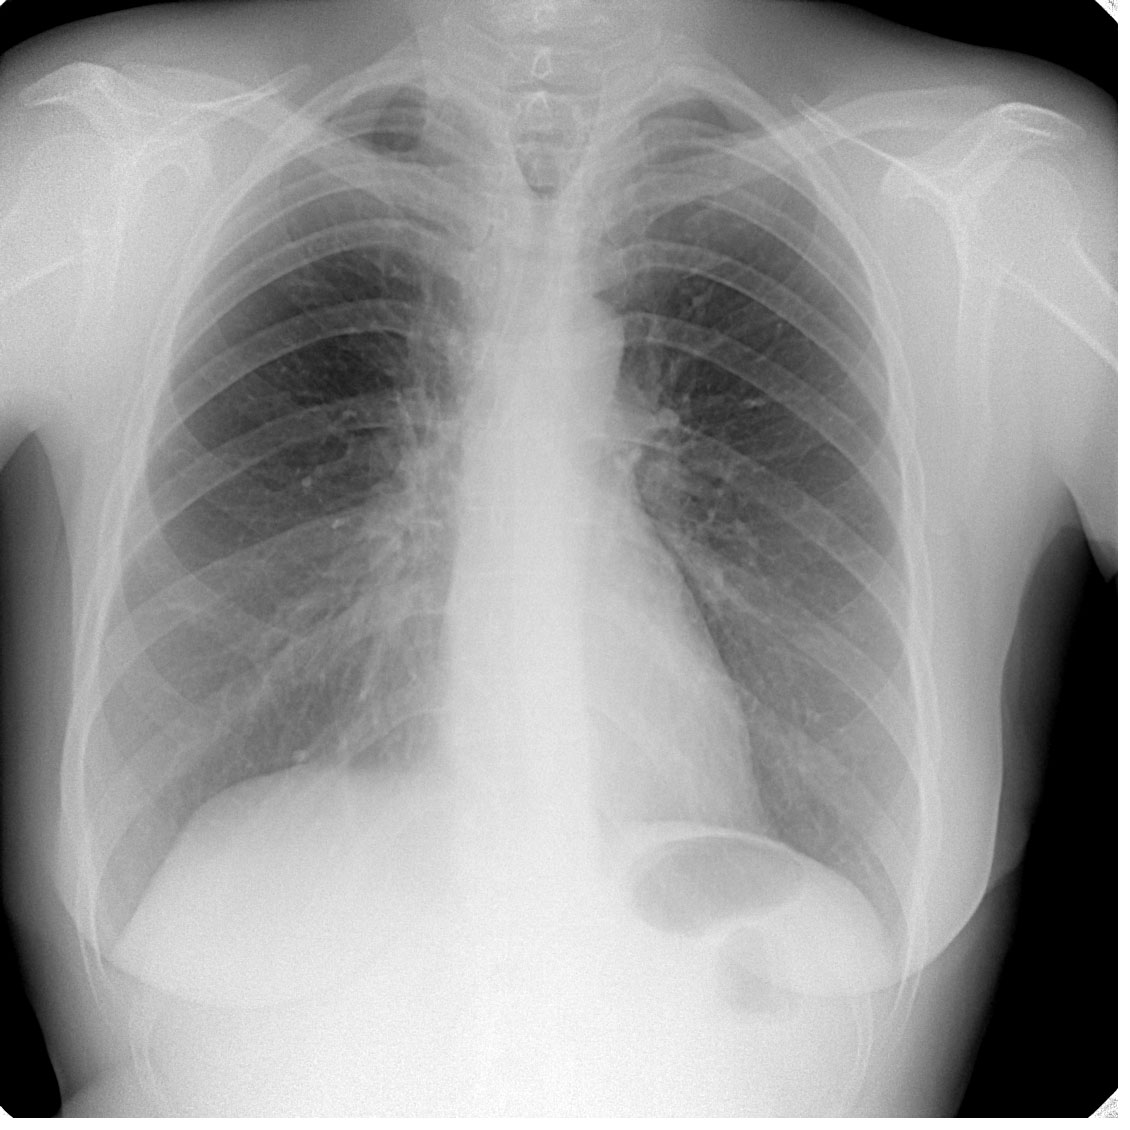

Чистый профосмотр

. Что-то задерживает взгляд. Что же?

Навскидку- глаз не зацепился.

Согласна с Любой- странно расширенный участок трахеи.

Трахеобронхомегалия?

Не-не. Сегодня не 1 апреля. Всё внимание верхнему средостению.

Могу добавить заднюю и боковую проекцию. И снимки прошлых лет. Что предпочтительнее?

Врождённая расщелина грудины, или стернокизис

Что-то не то с задним опорным комплексом верхнегрудных позвонков. Ламинэктомия как-будто?

Мы же угадываем? Пусть будет экстирпация гортани.

Гриша Хата сегодня просто отличник!

10 лет назад: Опухоль гортани T3N1M0. Расширенная ларингэктомия + лимфаденэктомия справа; Лучевая терапия.

И, как видим, без рецидива и процедива.